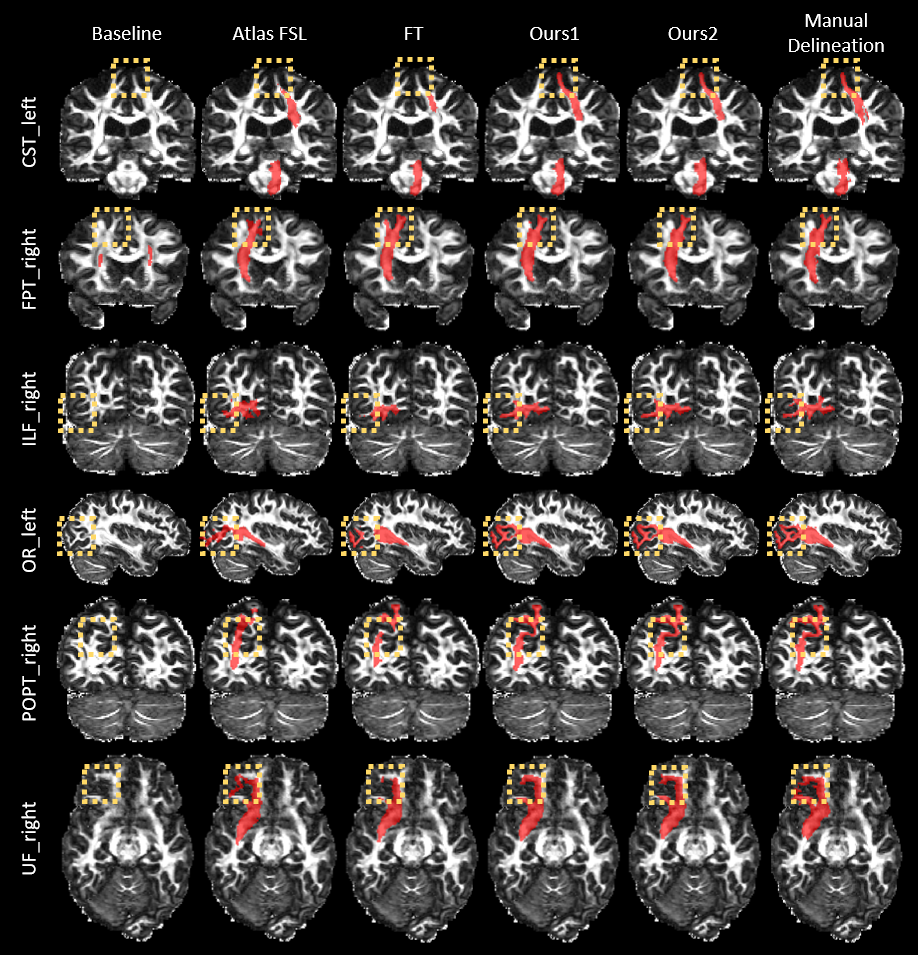

Figure 1: Cross-sectional views of the segmentation results (red) overlaid on the fractional anisotropy maps for representative test subjects and novel WM tracts. The manual delineations are also shown for reference. Note the highlighted regions for comparison.

The proposed method was first evaluated qualitatively. Cross-sectional views of the segmentation results for representative test subjects and novel WM tracts are shown in Fig. 1. The manual delineations are also shown for reference. It can be seen that the results of both of our strategies better resemble the manual delineations than the competing methods.